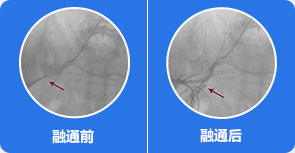

2血管疏通,解决血管供血问题

借助国家专利技术可视血堵融通术,打通股骨头血管管内各种类型淤堵损伤,解决血管供血问题,恢复股骨头血供。

治疗前:通过影像,可知道股骨头周边血管分布、病灶部位,血管哪里堵塞清晰可见

治疗中:旋股内侧动脉中的血脂、血栓逐渐被疏通

治疗后:通过融通术,旋股内侧动脉逐渐恢复血供,骨关节周围血流量加快,骨细胞供血恢复正常